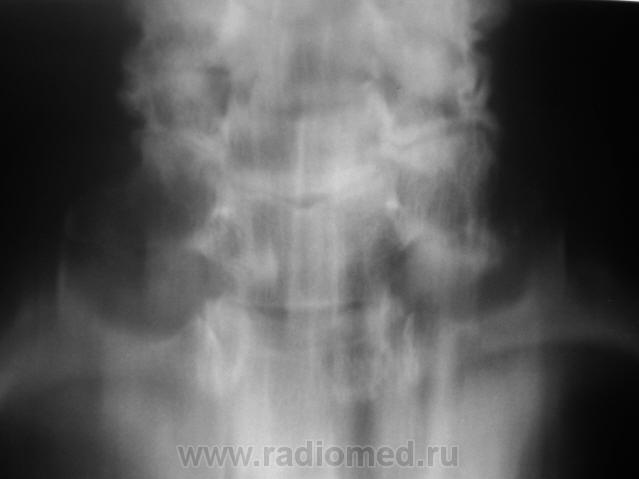

Или нео переднего средостения другой природы - тут только биопсия...

Загрудинный зоб либо тимома с озлокачествлением?